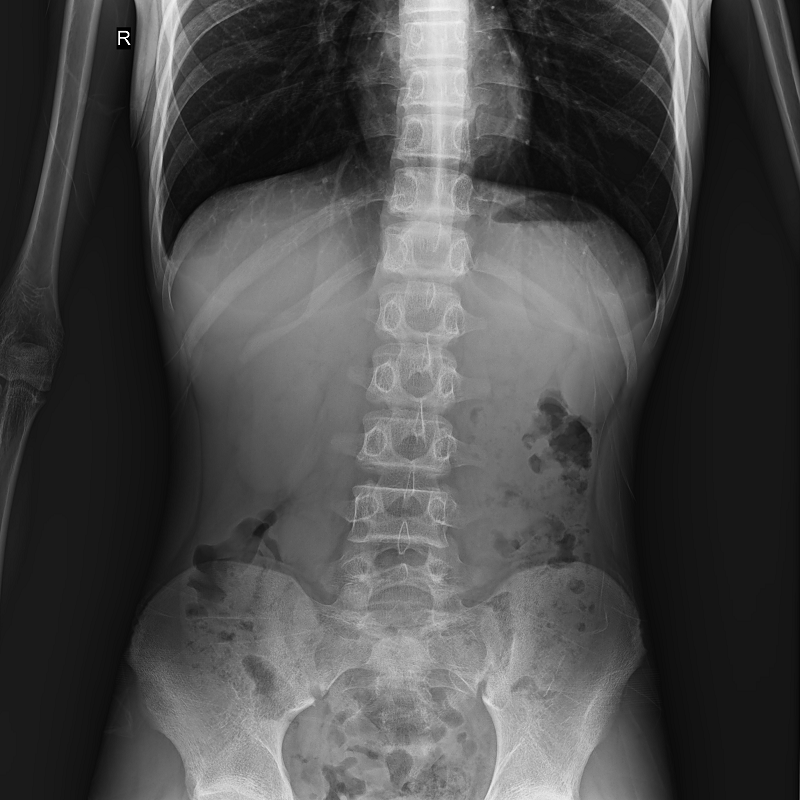

全自動(dòng)拼接

●呈現(xiàn)全下肢或全脊柱圖像

●在脊柱及下肢畸形矯正手術(shù)治療中,為術(shù)前方案制定和術(shù)后復(fù)查提供精準(zhǔn)測(cè)量

●有效解決傳統(tǒng)X光片不能一次成像問(wèn)題,為患者提供更加優(yōu)質(zhì)的醫(yī)療服務(wù)

Clinical picture

臨床圖片